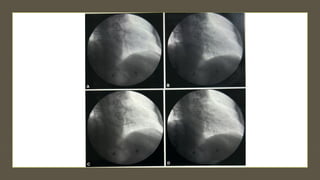

RIGHT IJV APPROACH

 After securing right IJV with a venous sheath,the preshaped 50 cm bioptome

is introduced pointing towards the anterior wall of the right atrium.

 In the mid right atrium, the bioptome is advanced slowly with

counterclockwise rotation.

 Continued rotation and slow advancement allow bioptome to enter into the

right ventricle and orient towards the septum.

 If entry into the RV remains difficult , then a Swan Ganz catheter or other

balloon floatation device may be used to define the pathway.